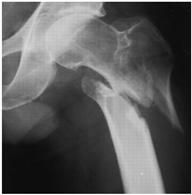

For X-ray 1, four scenarios were developed.![]() | Scenario 1: What would be your operation preference for a mobile patient aged 50–70 and with an ASA score of 1–2? Scenario 2: What would be your operation preference for a mobile patient aged 71 years or older with an ASA score of 1–2? Scenario 3: What would be your operation preference for a mobile patient aged 50–70 with an ASA score of 3–4? Scenario 4: What would be your operation preference for a mobile patient aged 71 years or older with an ASA score of 3–4? |